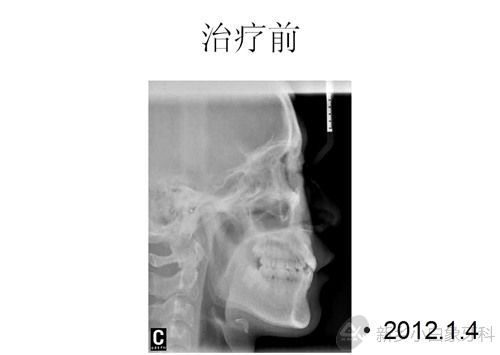

患者赵某某,男,21岁,感觉牙齿不齐,影响美观,于2012年1月4日来我院就诊。经检查,全口恒牙列,磨牙尖牙均中性关系,11牙冠发育畸形且远中扭转,12.22腭侧错位,13.23因间隙不足完全唇侧低位萌出,41.42完全舌侧位,35.45颌面中央有一凸形隆起,牙结石二度,牙龈红肿,探及出血,余未见明显异常。

问题清单:安氏一类错合;11发育畸形;35.45畸形中央尖;牙列拥挤;牙龈炎;11.21根尖处有两个多生牙。

治疗计划:全口固定矫治术;拔除14.24.35.45;排齐与整平牙弓;关闭拔牙间隙;调整咬合关系;11.21根尖处多生牙择期拔除;全口洁治。